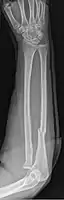

| Monteggia Fracture (type of ulna fracture) | |

- Monteggia fracture - a fracture of the near to elbow end of the ulna with the dislocation of the head of the radius at the elbow joint.[2]

Monteggia Fracture (fracture of proximal ulna)